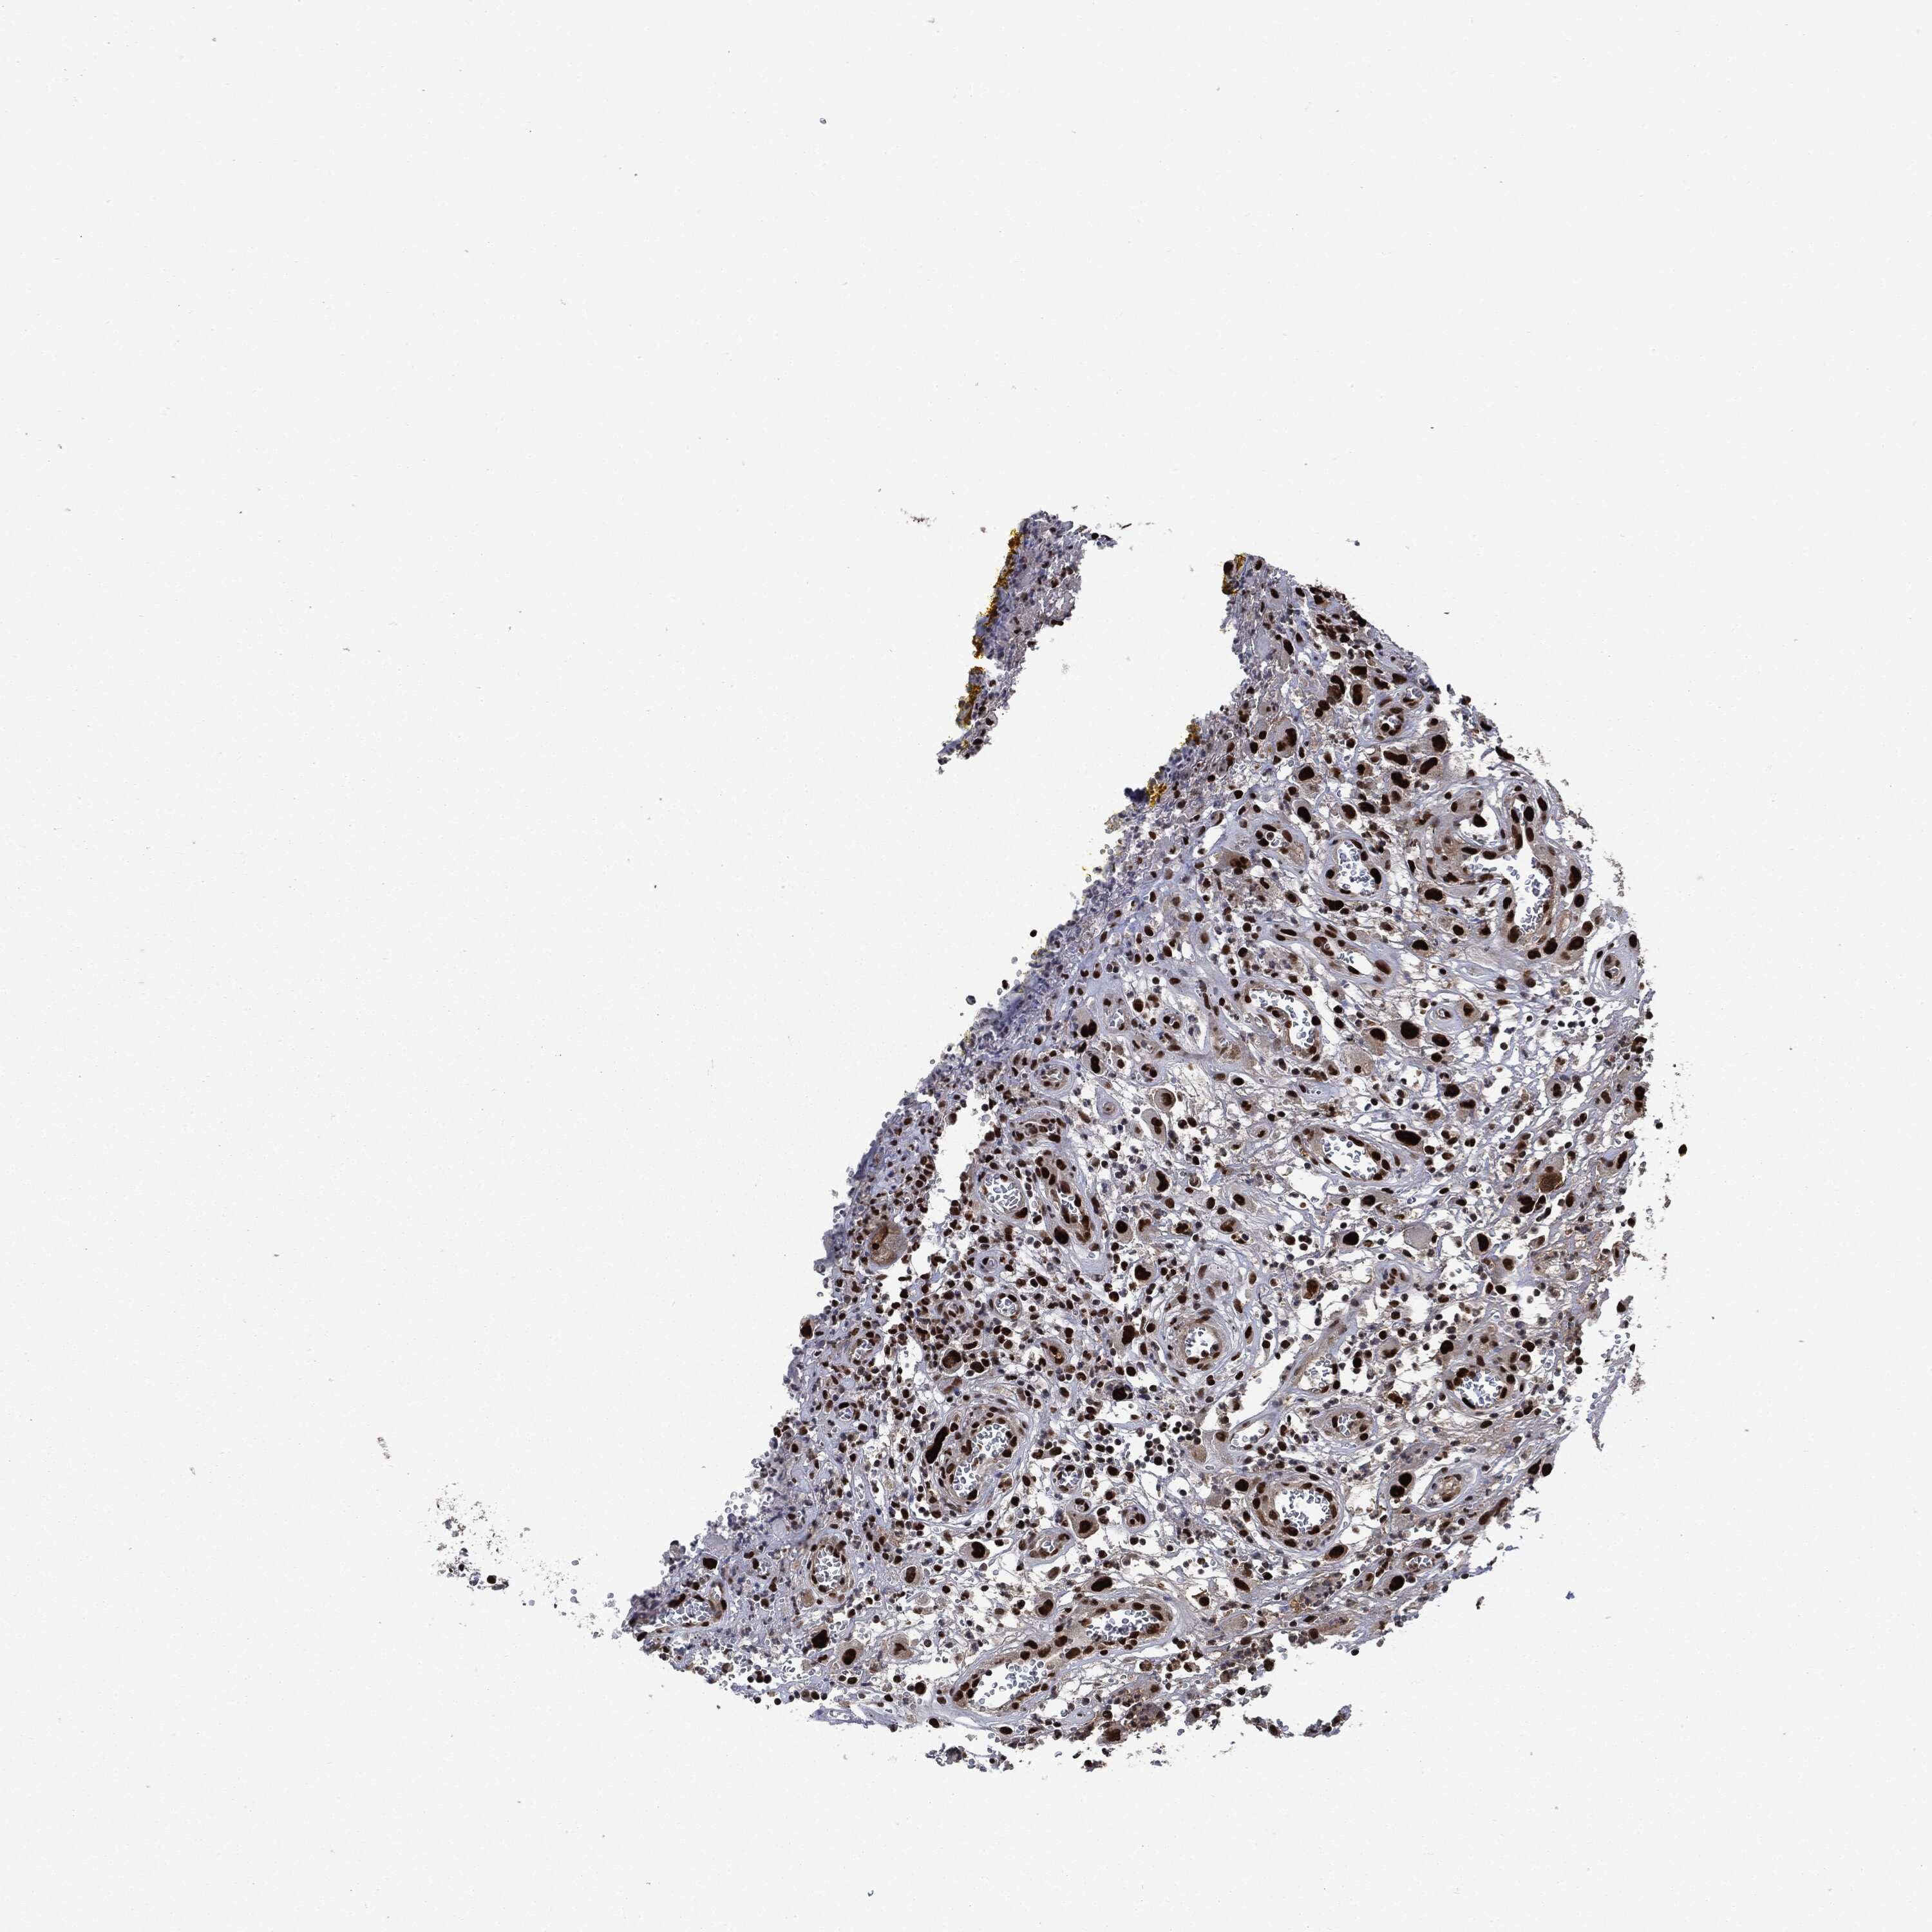

HEAD AND NECK CANCER - Protein expressioni

A mouse-over function shows sample information and annotation data. Click on an image to view it in a full screen mode. Samples can be filtered based on level of antibody staining by selecting one or several of the following categories: high, medium, low and not detected. The assay and annotation is described here.

Note that samples used for immunohistochemistry by the Human Protein Atlas do not correspond to samples in the TCGA dataset.

Antibody stainingi

Antibody staining in the annotated cell types in the current human tissue is reported as not detected, low, medium, or high, based on conventional immunohistochemistry profiling in selected tissues. This score is based on the combination of the staining intensity and fraction of stained cells.

Each image is clickable and will lead to virtual microscopy that enables deeper exploration of all samples and also displays staining intensity scores, fraction scores and subcellular localization as well as patient and tissue information for each sample.

HPA030521

HPA030522

HPA030523

CAB000148

CAB080240

CAB080241

CAB080242

Staining

High

Medium

Low

Not detected

Intensity

Strong

Moderate

Weak

Negative

Quantity

>75%

75%-25%

<25%

None

Location

Nuclear

Cytoplasmic/membranous

Cytoplasmic/membranous,nuclear

Squamous cell carcinoma, NOS

Squamous cell carcinoma, metastatic, NOS

Adenocarcinoma, NOS